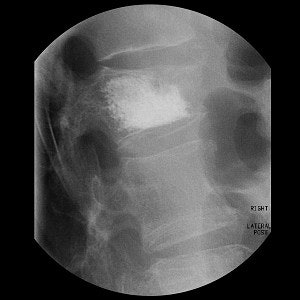

![]() ![]() |

Top, radiography of a compression fracture. Center, vertebroplasty needle insertion. Below, post-procedure. Images courtesy of Dr. Martin Radvany.